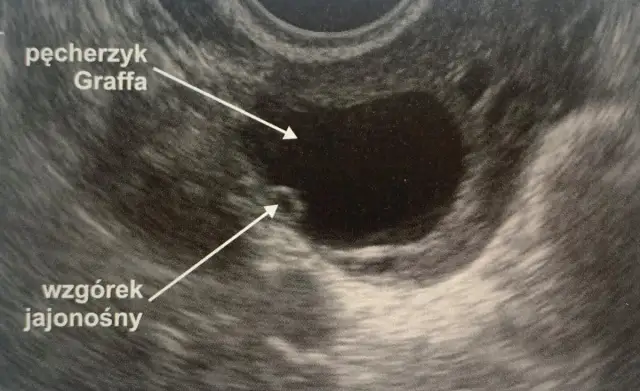

Pęcherzyk 18 mm: Kiedy owulacja? Przewodnik dla starających się o dziecko

Pęcherzyk 18 mm: dowiedz się, kiedy nastąpi owulacja i jak precyzyjnie zaplanować starania o dziecko. Sprawdź rolę endometrium i hCG!